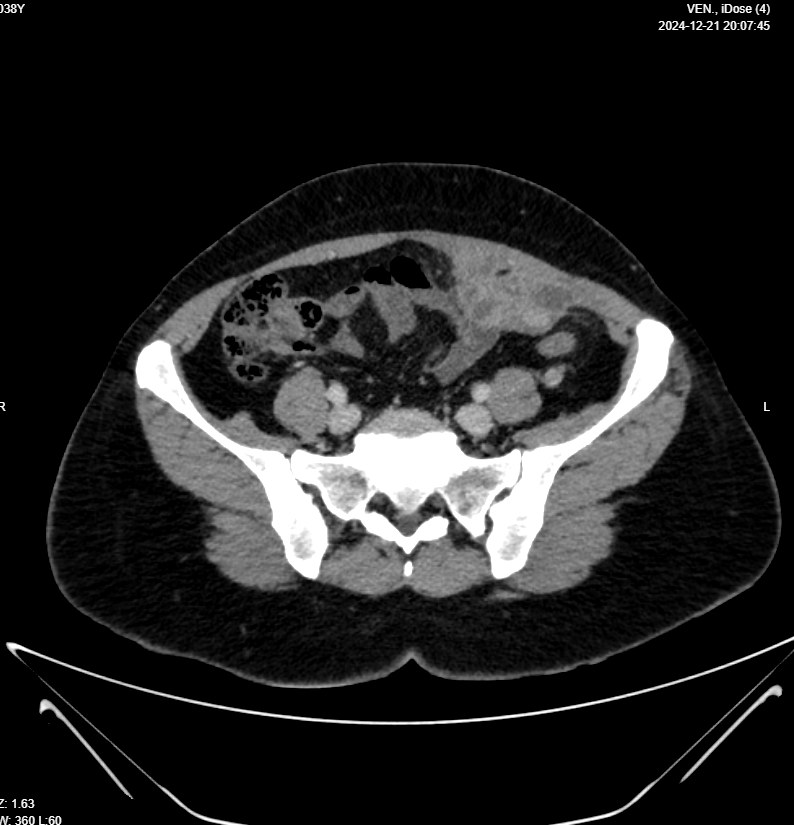

Chest, Abdomen & Pelvic CT With IV Contrast

Clinical data: Malignant LEFT OVARIAN MASS KINDLY FOR PRE RX STAGING

- Evidence of 6 X 4 X 3cm multilocular mass in Lt lower abdomen, arises from Lt adnexa “attached to uterus and Lt ovary”, invades posterior aspect of Lt rectus muscle, in contact with Lt inferior epigastric artery, also in contact with loop of small intestine with no frank invasion, this mass has surrounding fat stranding, which makes it possible to be infection like tubo-ovarian abscess, although malignancy can not be excluded, lab studies and MRI is suggested for further evaluation please.